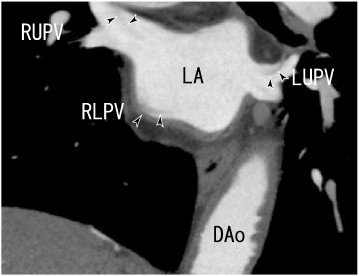

A 76-year-old man experienced chest pain. He had no symptoms of cerebral infarction or lung cancer. The patient had no history of smoking or symptoms of tachypnea, fever, cough, sputum, palpitation or cerebral infarction. The lung examination did not reveal decreased breath sounds, lung crackles or wheezing. The cardiac examination did not demonstrate a heart murmur or arrhythmia. He had no history of recurrent atrial fibrillation or airway infections, and he was not treated with antithrombotic or anti-platelet drugs. The chest roentgenogram did not reveal lung cancer. The serum d-dimer level was < 0.5 μg/mL (normal < 1.0 μg/mL); the protein S activity was 91% (normal 60–150%); and the protein C activity was 66% (normal 64–146%). 64-MDCT was performed to check for coronary artery stenosis, and it revealed thrombi in the left upper and left lower pulmonary veins (LUPV and LLPV), the right upper and lower pulmonary veins (RUPV and RLPV), and the left atrium (LA) as defects of contrast enhancements (Fig. 1, Fig. 2, Fig. 3, Fig. 4 ;  Fig. 5). The LA thrombi seemed to be connected to the thrombi of four pulmonary veins, potentially representing a network of thrombi.

A 64-slice multidetector CT (64-MDCT) scan showed coronal images of thrombi in ...

Fig. 1.

A 64-slice multidetector CT (64-MDCT) scan showed coronal images of thrombi in the right and left upper pulmonary veins (RUPV and LUPV) and in the left atrium (LA), which seemed to be connected to thrombi in the right lower pulmonary vein (RLPV) (arrowheads). DAo: descending aorta, LA: left atrium, LUPV: left upper pulmonary vein, RLPV: right lower pulmonary vein, and RUPV: right upper pulmonary vein.